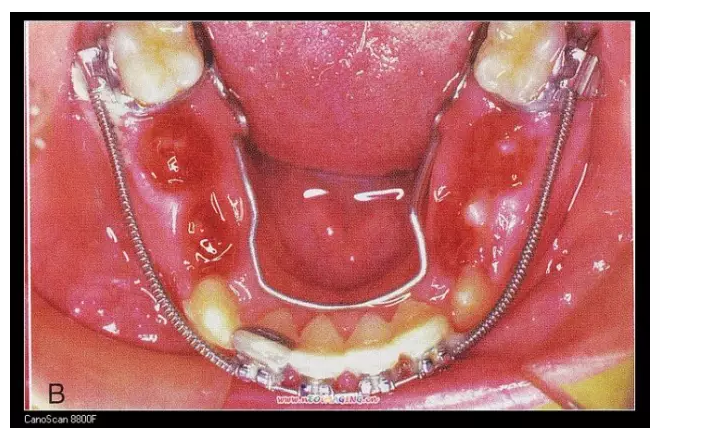

三、擴(kuò)弓器

很多牙列不齊常伴隨牙弓過窄,所以擴(kuò)弓器是正畸醫(yī)生的好伙伴,它可以以多種形態(tài)和您見面。